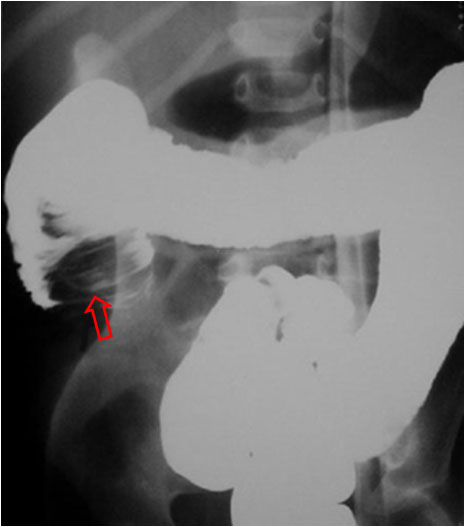

SIGNO DE LA DISECCIÓN DE LA INVAGINACIÓN

Signo de invaginación intestinal del lactante, visto en el enema opaco, que hace referencia al avance del contraste baritado entre el asa invaginante y el asa invaginada (flecha).

Hay otro buen ejemplo en esta página: http://www.mypacs.net/cases/40200015.html.